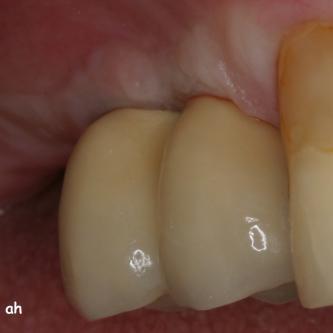

Exemple 7: Un implant au niveau de la deuxième prémolaire inférieure gauche.

Exemple 7: Le moignon vissé sur l'implant.

Exemple 7: La couronne en place

Exemple 7: vue depuis dessus